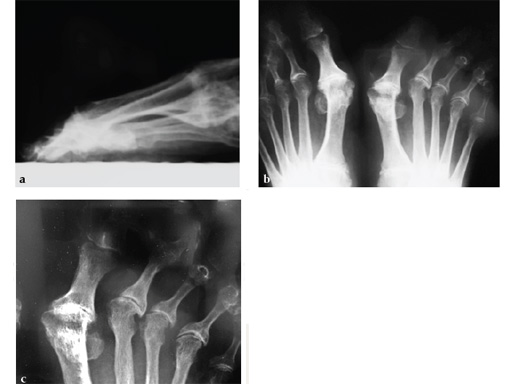

A 57-year-old woman has suffered rheumatoid arthritis for several years. She presented with pain and deformity in the left forefoot moreso than in the right. Clinical examination reveals severe hallux valgus deformity and dislocation of MP joints 11 through V, with synovitis.

Case provided by Juan Bernardo Gerstner, Cali, Columbia

A dorsal transtendinous approach was used and reaming of the first MT head and basal articular surface of the proximal phalanx was performed with the new reamers (see Fig. 3a-b).

A left MP fusion was performed as well as a II to V MT head resection arthroplasty, and fixed with K-wires for 4 weeks (see Fig. 4a-b). The patient was weight bearing immediately with wooden shoes and K-wires were removed 4 weeks postoperatively.